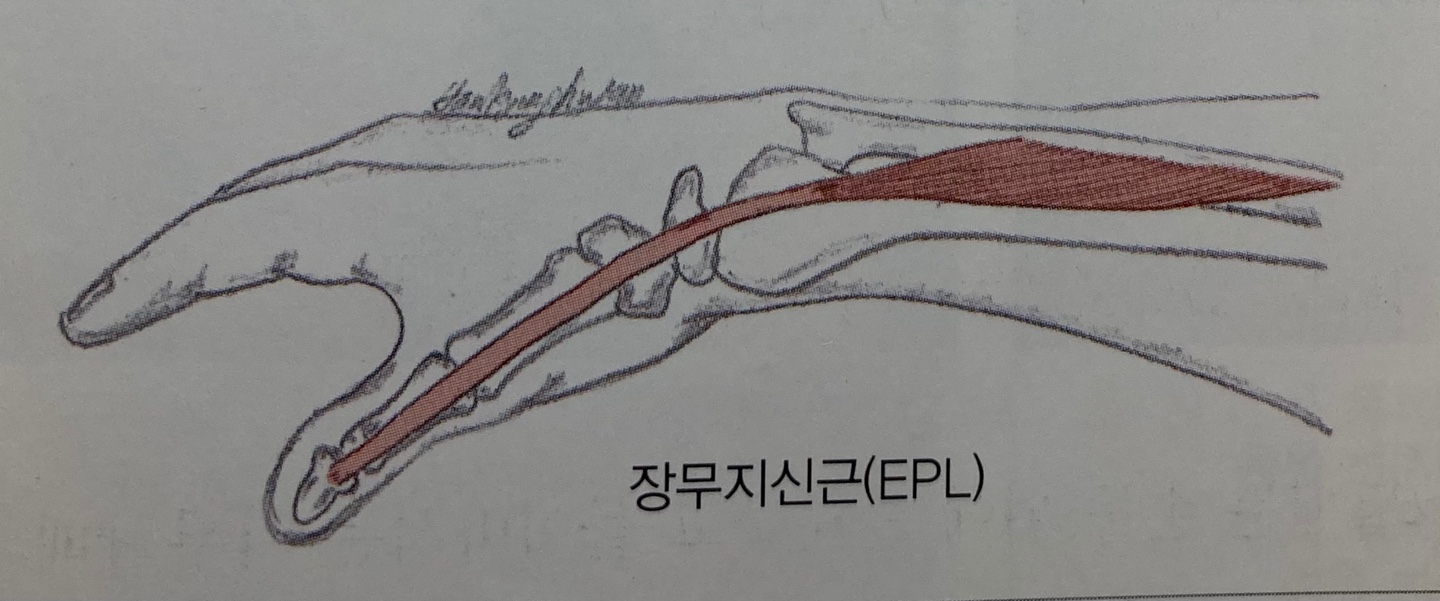

| 3. 장무지신근(Extensor policis longus) 기시점(Origin) : - 척골 원위부의 전면 1/3지점에서 장무지외전근의 기시부에 걸친 구간 - 골간근막(Interosseous membrane) 정지점(Insertion) : 무지 원위지골(Distal metacarpal) 기저부의 배면 신경지배(Innervation) : 요골신경(Radial nerve), C6, C7, C8 작용(Action) : - 무지의 지절관절 신전과 중수지절과 수근중수관절의 신전을 보조 - 손목의 외전과 신전에도 영향을 준다 |